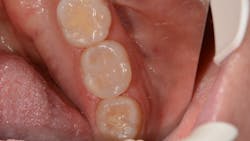

The lower left second molar was prepared for a class II composite restoration (figure 3). A sectional matrix band was placed and wedged. The preparation was etched, and adhesive was placed and cured. The VisCalor bulk was heated in the heating gun and then dispensed into the base of the box while in its flowable state. Note the complete adaptation of the material to the walls ofEditor's note: This article appeared in the November 2021 print edition of Dental Economics.